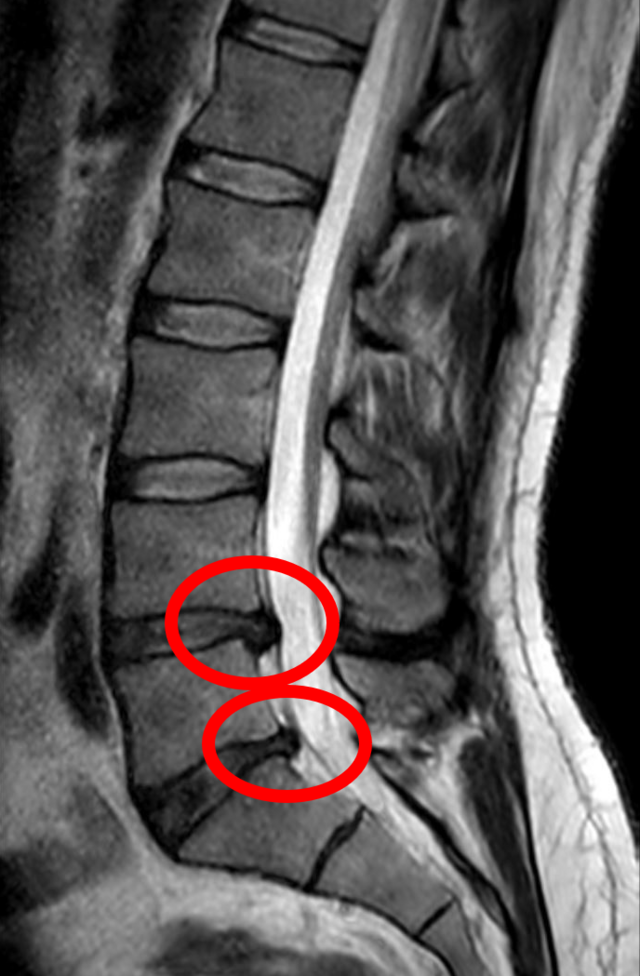

허리디스크(추간판 탈출증)는 척추 뼈 사이에서 충격을 흡수하는 디스크(추간판)가 제자리를 벗어나 주변 신경을 압박하는 상태입니다. 신경이 눌리기 때문에 허리뿐 아니라 엉덩이, 다리, 발끝까지 통증이나 저림이 퍼지는 것이 가장 큰 특징입니다.

허리디스크는 근육통과 달리 신경 압박 증상이 동반되는 것이 핵심입니다. 디스크가 신경을 누르기 때문에 허리 통증보다 다리 통증이 더 심한 경우도 있습니다.